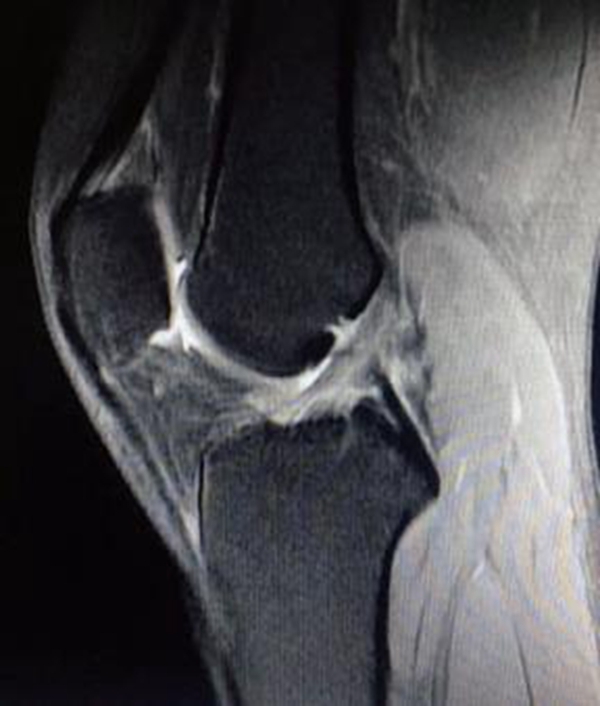

由于ACL的解剖特点,常规MRI扫描方向无法满足精确诊断的需要,因此沿ACL的方向扫描对于诊断有重要的作用。MRI影像上正常的ACL是起自股骨外侧髁内侧面,斜向前内侧走行,止于胫骨髁间隆起前方的一条边缘清晰、光滑、具有张力感的低信号带(图7)。连续性中断是ACL断裂最直观的表现(图8)。

Lee等提出ACL断裂的MRI诊断标准: ①ACL前缘呈不规则波浪状;②T2WI成像中ACL信号内有高信号;③矢状面上ACL信号不连续;④当伴有上述征象之一时,前部呈弓状的PCL可支持ACL撕裂。

图7 正常ACL的MRI影像